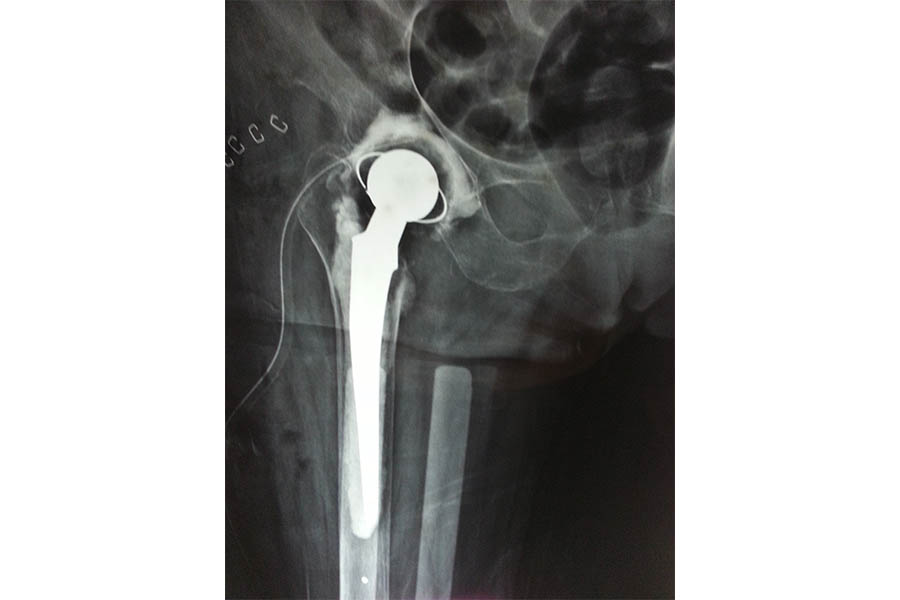

Difficult Replacement

Case 1